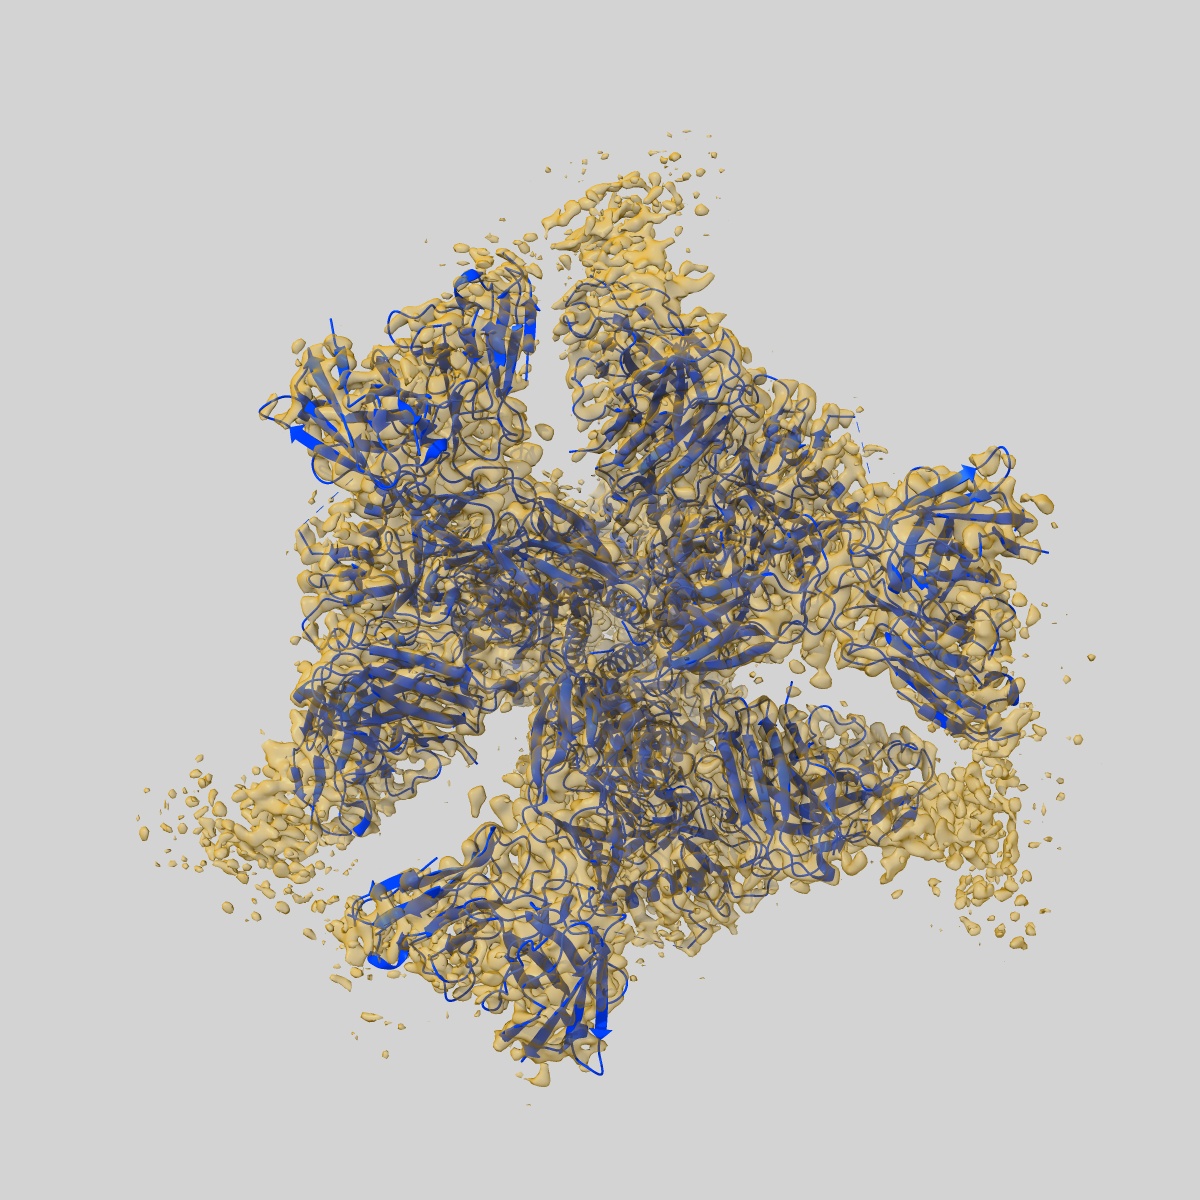

HIV-1 Env BG505 SOSIP.664-dPG-His in complex with PGT122 and 3BNC117 Fabs

Single-particle3.2 Å

Sample: HIV-1 Env BG505 SOSIP.664-dPG-His in complex with PGT122 and 3BNC117 Fabs

Fitted models: 9ogu